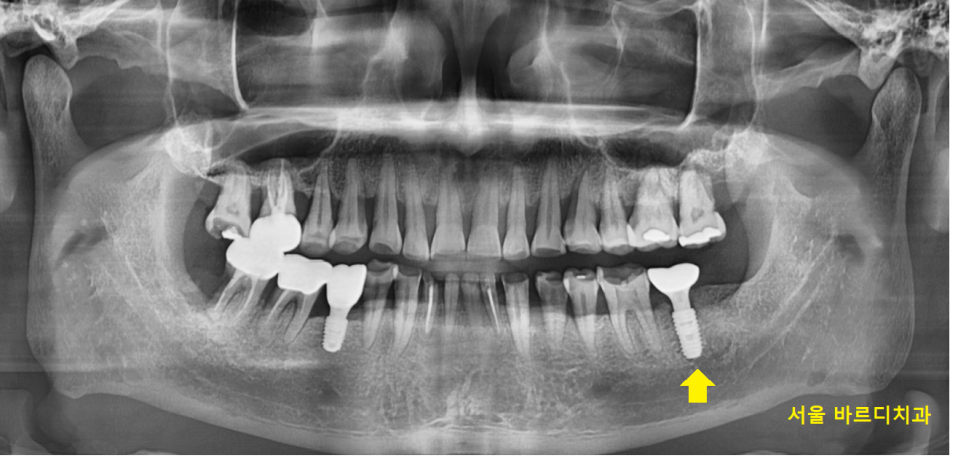

24.02.03

풍산동 치과에서

치료를 완료하는 몇개월 사이

치아가 더 깨졌습니다.

어금니 금감 진행된거죠.

우선은 불편하신건 없으시다하여

임플란트 관리 해드리면서

지켜보기로 하고

치료를 마무리해드렸습니다.